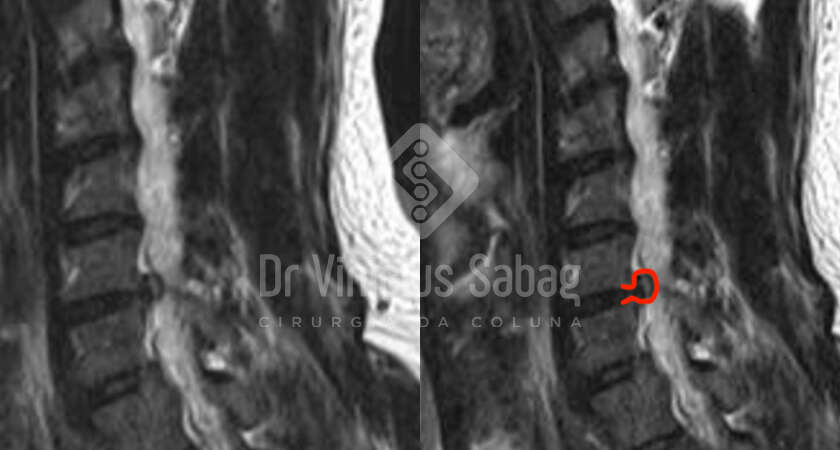

Paciente de 74 anos com queixa de dificuldade progressiva para andar. O quadro teve início há alguns meses com fraqueza nas pernas, limitando inicialmente sua caminhada a cerca de 10 minutos.

Com a evolução dos meses, a distância percorrida foi reduzindo progressivamente. O paciente passou a apresentar limitação para andar mais que um quarteirão,…